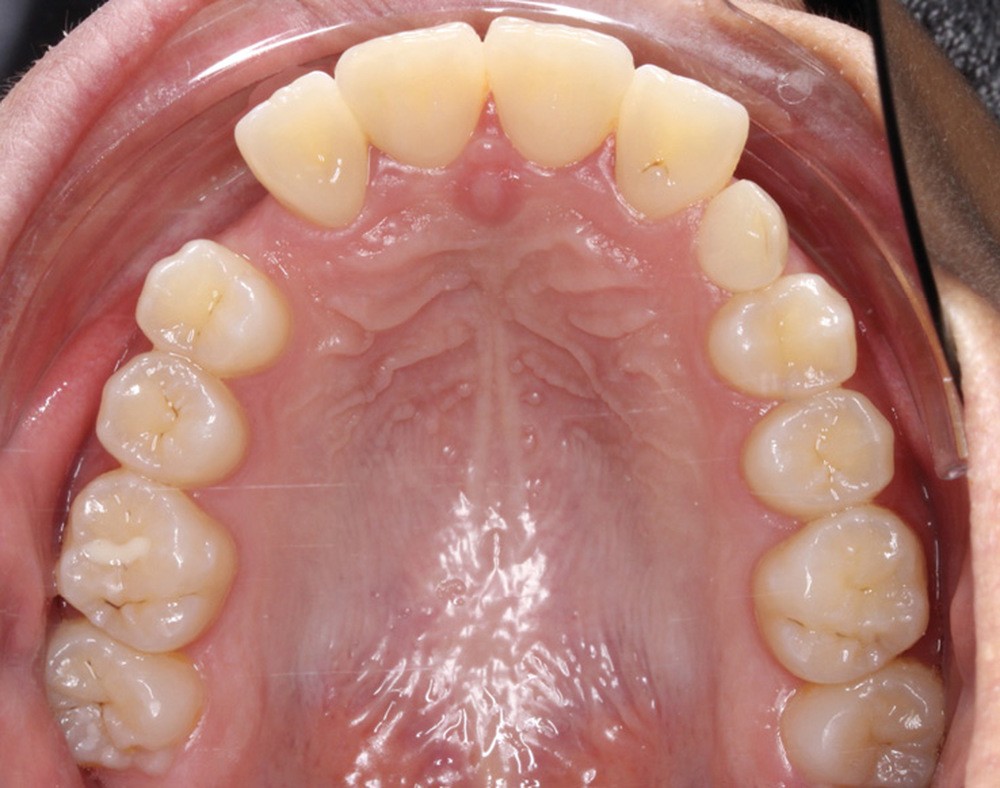

Les caches esthétiques ont été progressivement diminués jusqu’à leur suppression complète. Une fois l’alignement des canines obtenu, la prise en charge de 11 et 21 sur un NiTi .014 a débuté. Des forces très douces avec un contrôle radiologique tous les trois mois ont ensuite permis l’alignement et la fermeture des derniers espaces maxillaires. Une coronoplastie soustractive de 13 et 23 a été réalisée pour les transformer en 12 et 22. La vitalité de 11 et 21 a été conservée. En contention, deux fils collés ont été mis en place (13-23 et 33-43) ainsi qu’une gouttière thermoformée maxillaire amovible à port nocturne. Le traitement a duré vingt-neuf mois (fig. 5a-f).

Le traitement a permis d’améliorer l’environnement parodontal et de mettre en place les canines incluses tout en préservant au maximum les incisives centrales déjà résorbées et en assurant un résultat esthétique pour la patiente.